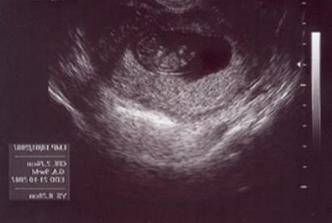

Na svet by som mala prísť 17.10.2007, budem sa volať Emka (v prípade, že sa pani doktorka pomýlila, tak Palinko) a maminka s tatinkom sa na mňa stráááášne tešia!